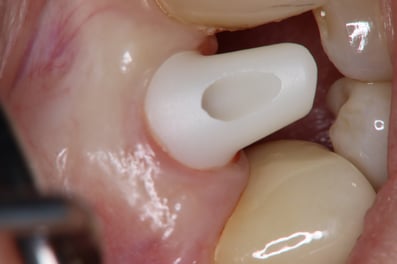

抜歯した直後にインプラントを埋入し、仮の歯を作製、唇側の骨のボリュームを保つために人工骨と結合組織を同時に移植する非常に優れた方法です。

しかし、非常に難易度の高い手術になります。